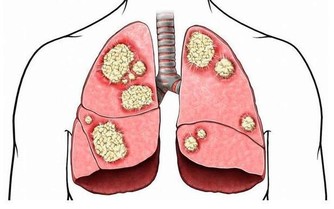

如今人們對於定期體檢更加重視,很多女性在體檢的時候都檢查出自己患有子宮肌瘤,雖然大多數都是良性的,但也有極少數會存在惡變的可能,嚴重的話還會發展為癌症。

子宮肌瘤主要是由於雌激素過高所導致的,在絕經之後,